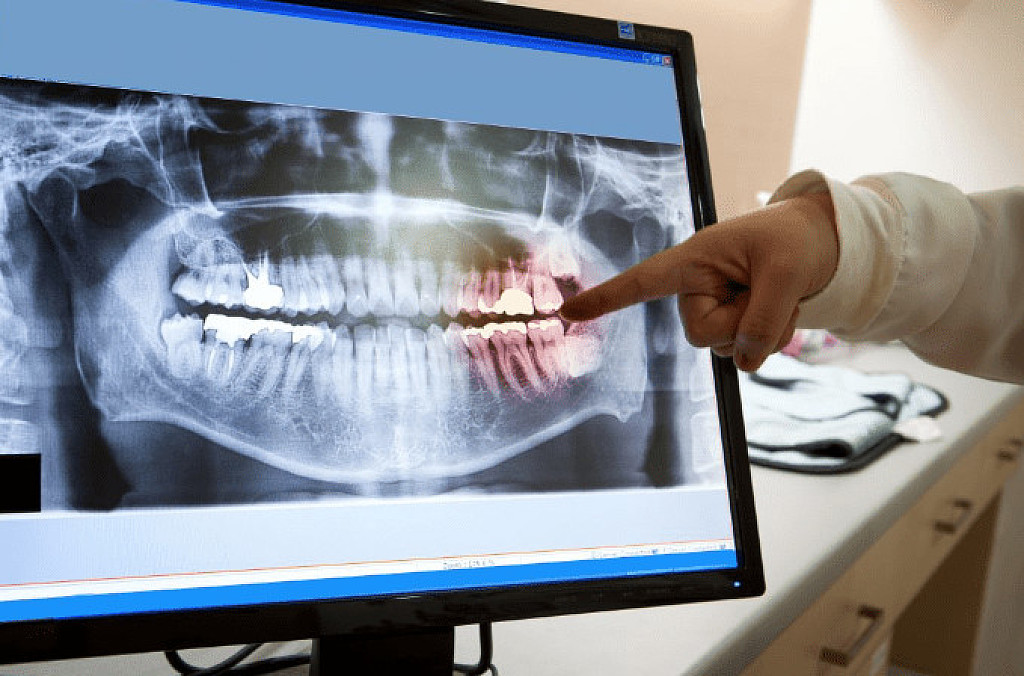

Panoramic X-Ray:  This is a type of sizeable dental X-ray that requires a separate machine. The X-ray provides a detailed image of all the teeth in both lower and upper arches, along with the bone and supporting structures. They are usually used for extensive dental work like multiple extractions, braces, dental implants, etc.